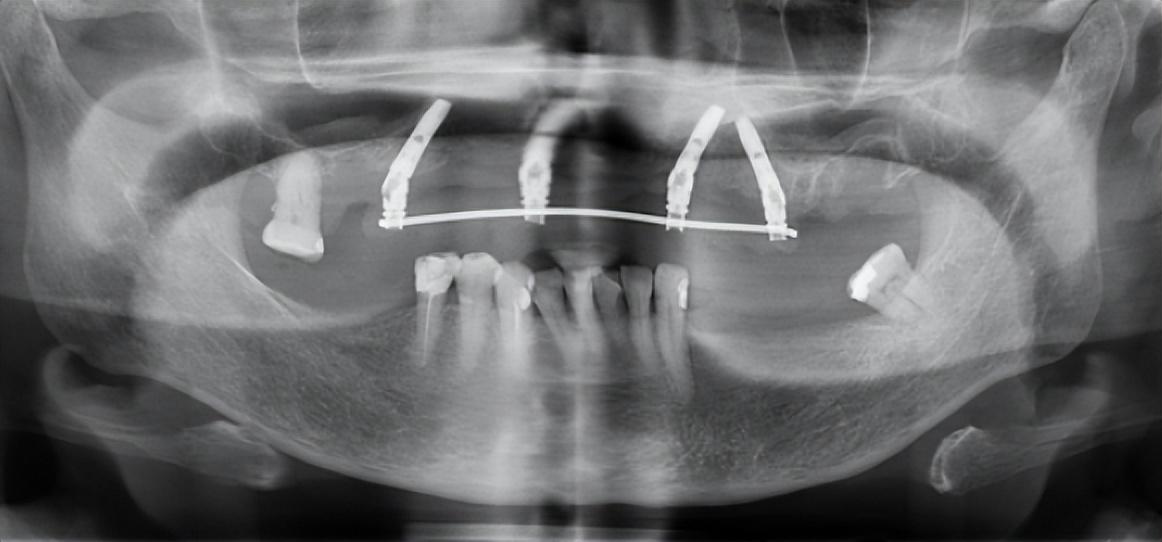

口腔種植的費(fèi)用大致分為種植體、牙冠和醫(yī)療服務(wù)三個(gè)部分,相比耗材,降低種植牙醫(yī)療服務(wù)價(jià)格,難度要大得多,一些公立醫(yī)院種植牙醫(yī)療服務(wù)部分的平均費(fèi)用超過(guò)6000元,一些省市甚至超過(guò)9000元。此前,醫(yī)保局開(kāi)展口腔種植收費(fèi)和醫(yī)療服務(wù)價(jià)格調(diào)查登記,初步結(jié)果顯示,醫(yī)療服務(wù)部分的費(fèi)用高是種牙貴的重要原因之一。

綜合患者、醫(yī)療機(jī)構(gòu)等多方意見(jiàn)后,三級(jí)公立醫(yī)院?jiǎn)晤w常規(guī)種植的醫(yī)療服務(wù)價(jià)格調(diào)控目標(biāo)確定為4500元,包括門診診查、生化檢驗(yàn)和影像檢查、種植體植入、牙冠置入等費(fèi)用,但不含種植體和牙冠的費(fèi)用。